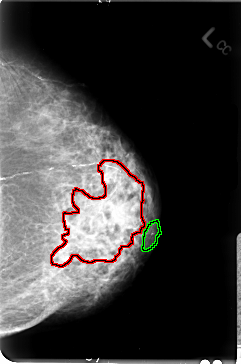

B_3027_1.LEFT_MLO

LEFT_MLO LINES 4696 PIXELS_PER_LINE 3184 BITS_PER_PIXEL 12 RESOLUTION 50 OVERLAY

FILE: B_3027_1.LEFT_MLO.OVERLAY

TOTAL_ABNORMALITIES 2

ABNORMALITY 1

LESION_TYPE MASS SHAPE IRREGULAR MARGINS ILL_DEFINED

ASSESSMENT 4

SUBTLETY 4

PATHOLOGY MALIGNANT

TOTAL_OUTLINES 1

BOUNDARY

ABNORMALITY 2

LESION_TYPE CALCIFICATION TYPE PLEOMORPHIC DISTRIBUTION CLUSTERED